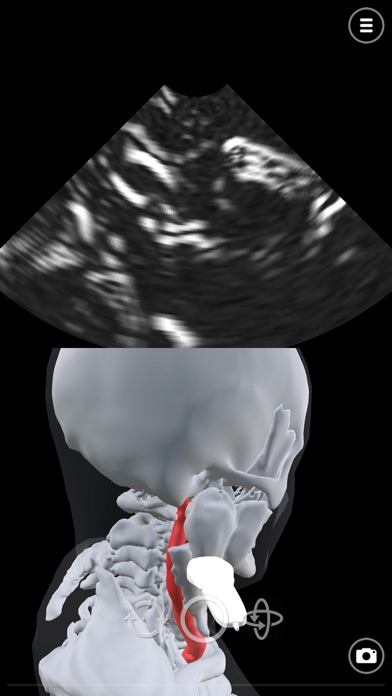

Learn ultrasound in a virtual ultrasound simulator. Deepscope ultrasound virtual learning modules are created to help learn the techniques of ultrasound.

-Anatomy relevant to the ultrasound scan examination

The ultrasound simulator uses advanced computer graphics techniques simulate sound waves. The sonogram is created as a result of these simulations.